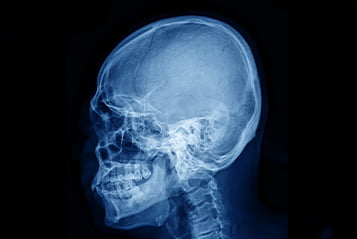

Urazów czaszkowo-mózgowych